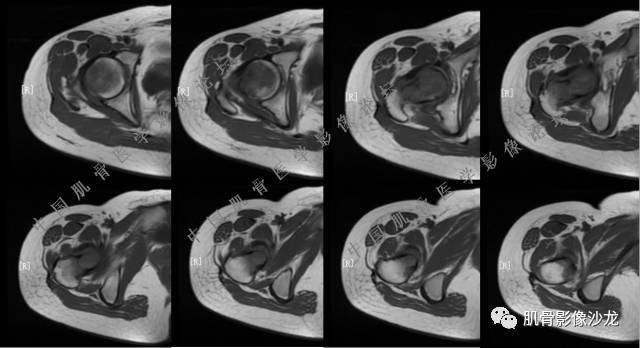

张小林 20:13 磁共振有双低信号,结合CT确实要考虑有纤维成份。

夏威夷的风 20:15 T1WI

Echo 20:16 软组织肿块突破了骨皮质

Echo 20:23 我个人觉得,17岁男性,病灶发生在原干骺端区域,溶骨性骨质破坏,似有肿瘤骨,有软组织肿块形成,从常见病发生率来说,骨肉瘤还是要考虑的

葛英霖 20:24 这个部位有一个需要鉴别的就是软骨母

葛英霖 20:26 可以发生在干骺端